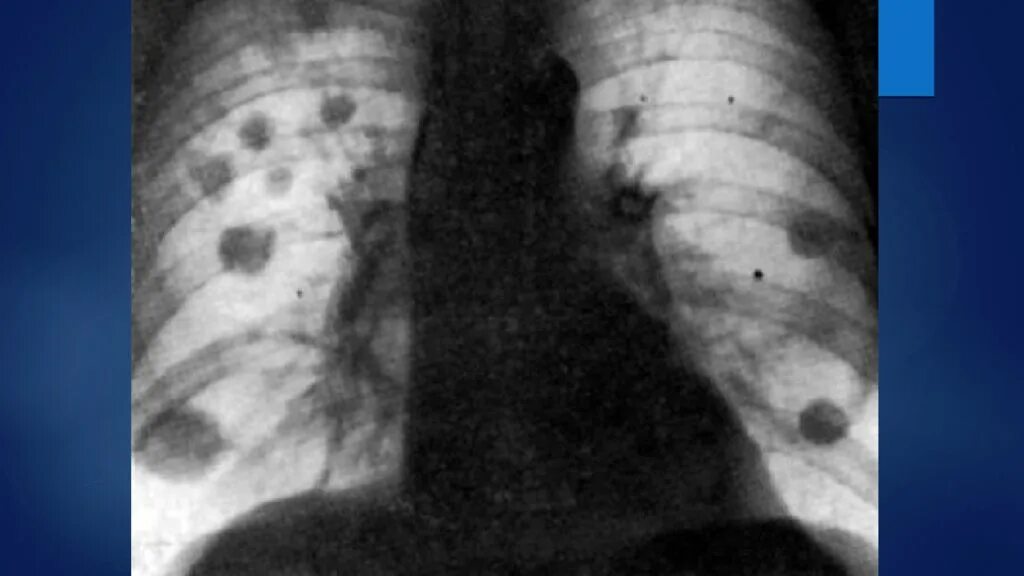

Поражение легких при туберкулезе